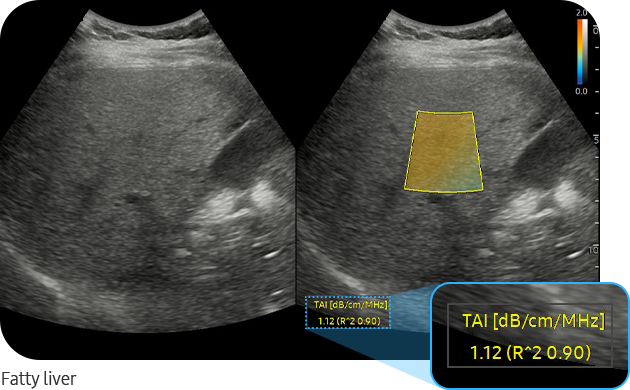

TAI™ (Tissue Attenuation Imaging) is a tool that quantitatively measures the attenuation of ultrasound signals received from the liver. TAI™ quantifies attenuation based on changes in the center frequency under the optimal transmission and reception conditions.